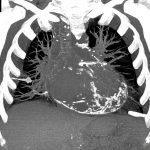

Hình ảnh bất thường bóng tim trên phim X-quang ngực.